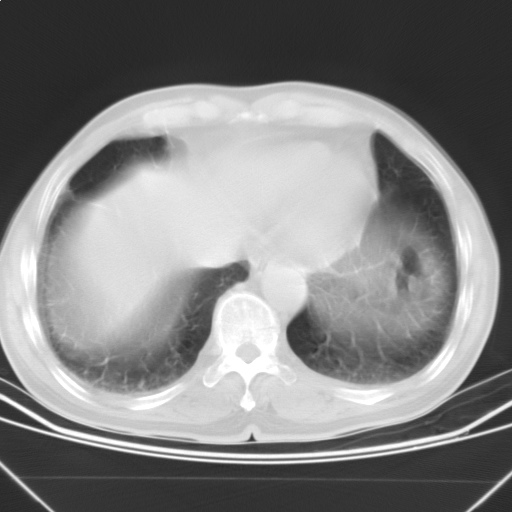

以下是引用随光逐影在2009-5-1 13:53:00的发言:[br]考虑为:1)两肺血行播散型肺结核;2)右肺下叶炎症感染。3)右侧胸膜增厚。